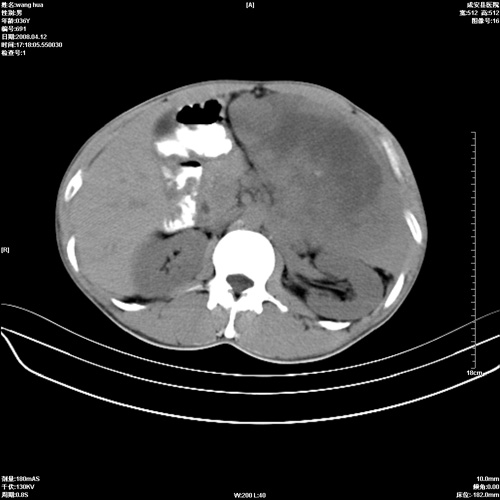

标题: CT12809:男36岁,自感上腹胀5天,B超诊断为脾肾之间占位,血 [打印本页]

标题: CT12809:男36岁,自感上腹胀5天,B超诊断为脾肾之间占位,血

请各位老师先分析一下定位 明天做增强

确实需要强化!先大胆预测一下,来源于脾脏的占位,血管瘤或淋巴瘤可能性大。

脾脏肿瘤,有钙化,增强再说

脾脏病变,密度不均,可见钙化,考虑脾血管瘤,建议增强

脾脏明显增大,其内见巨大低密度灶,境界不清,病史较短,考虑恶性病变脾血管内皮细胞肉瘤可能。建议增强扫描与脾脏淋巴瘤及血管瘤鉴别。